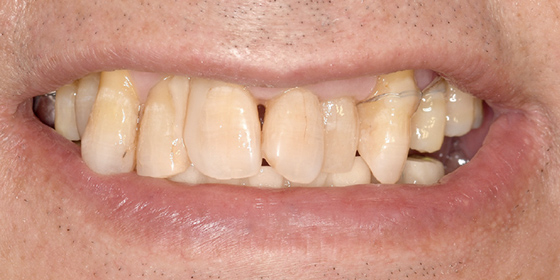

治療前

この症例では下顎の歯周病が特に進行していて、歯がクラグラで噛みにくい為、下の歯を抜歯してオールオン4で治療、上は特に歯周病が進行している左側の大臼歯を抜歯して経過観察することにしました。